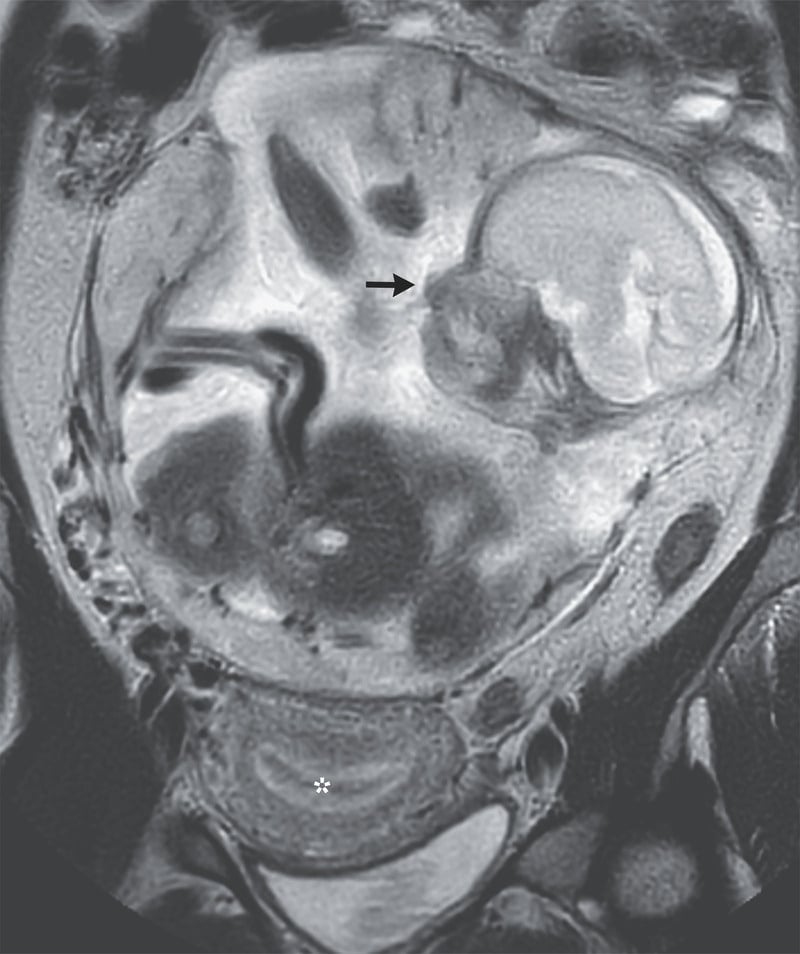

Перші ж обстеження у відділенні невідкладної допомоги приголомшили лікарів. Просто у черевній порожнині – між шлунком і кишківником – у жінки розвивалося дитя.

Цього разу жінці поставили діагноз – черевна вагітність. Це вкрай рідкісний різновид позаматкової вагітності. Плід нормальних для свого терміну розмірів розмістився у черевній порожнині в безпосередній близькості до життєво важливих органів. Плацента кріпилася до верхньої частини таза.

На 29-му тижні вагітності провели лапаротомію з пологами, емболізацію артерій плаценти та часткове видалення плаценти.